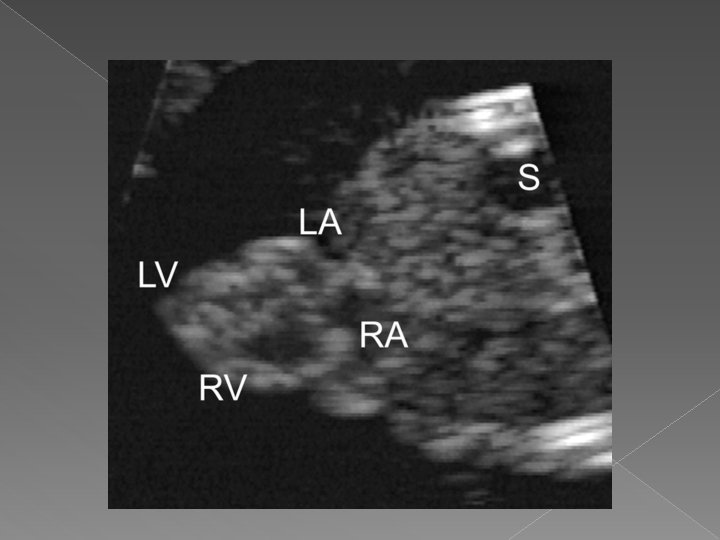

� Heart › A 4 chamber view should be visualized › Includes the RA, LA, RV, and LV › The rt. & lt. pulmonary vein, descending aorta, and lungs may also be visualized

Four chamber view › The 4 cv is the single most important image of the fetal heart. › Normal features are: �Apex of heart points 45 degrees to left anterior chest wall �Ventricles approx. the same size (right can be larger than left in pregnancy) �Flap of foramen of ovale opens into left atrium �Prominent moderator bands present in apex of right ventricle �Valves separate both atria from ventricles

� Normal orientation of the 4 chamber heart view within the fetal chest: the heart should take up 1/3 of the chest cavity with the apex pointing to the left chest wall.

Ectopia Cordis In ectopia cordis, all or part of heart is located outside of chest cavity. It is frequently associated with intra-cardiac anomalies and omphalocele in Pentalogy of Cantrell. Sonographic Findings: � Small thorax � Extension of soft tissue outside thoracic cavity in which cardiac activity is noted.